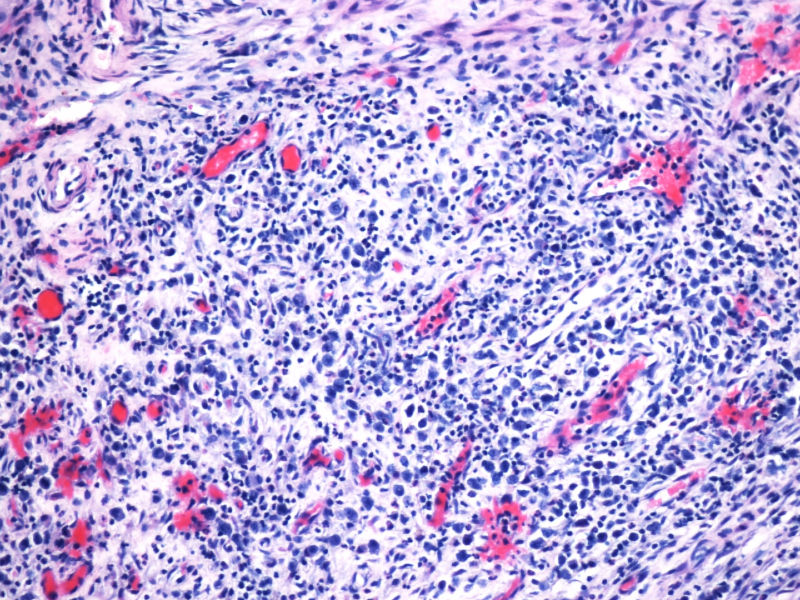

形态学hallmark 细胞显示不是很清晰,大的肿瘤细胞如果在ALCL和HL之间选择可能不容易,但HL的肿瘤细胞形态学特点的范围比较狭窄,而ALCL可能具有更广泛的形态学范围,细胞大小形态以及典型hallmark cell的多少有时很难确定。如果只看HE,觉得ALCL的可能会安全一点,当然我个人经验不足,可能理解得比较肤浅。

本例CD68的表达也许很重要,HL可以有严重的炎症背景,但背景细胞是否会出现如此明显CD68阳性细胞,还请各位老师教我;而ALCL CD68大概可以阳性。另外就是哪些细胞是肿瘤细胞的问题了,可能未必局限于CD30阳性的大细胞吧。

本例全B,全T缺失,使诊断很困难,淋巴瘤范围内一般考虑①HL;②浆细胞分化的肿瘤如浆细胞骨髓瘤或浆母细胞瘤;③ALCL. 以下为鉴别:

1.关于CD15:可见于HL,偶尔(WHO: rarely)见于ALCL,甚至可意外地或异常地(WHO: exceptionally)见于外周T,非特指.

2.关于PAX5:应该是HL和ALCL鉴别非常好的标记。WHO: The B-cell nature of HRS cell is further demonstrable in approximately 95% of cases by their expression of the B-cell specific activator protein PAX5. 本例PAX5阴性,重点就只有放在ALCL上了。

3.关于CD43: 对比CD43和CD3的结果,并不能否认ALCL,甚至还提供了一个线索就是CD3- 是由于肿瘤细胞“改头换面”缺失表达造成的,如果追加CD2,4,5等可能就会使肿瘤“原形毕露”了。

最后,ALK+可证实以上的推断。